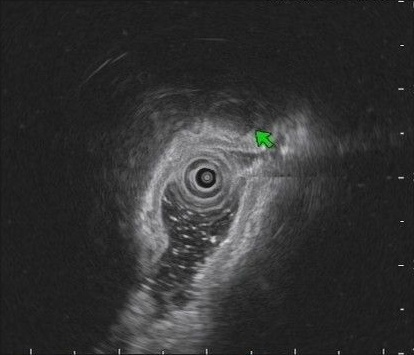

US imaging presents a substantial domain gap compared to other medical imaging modalities; building an US-specific foundation model therefore requires a specialized large-scale dataset. To build such a dataset, we crawl a multitude of platforms for human medical US with instance annotations and open-access availability: Papers with Code, Google Dataset Search, GitHub, Google Scholar, Kaggle, ResearchGate, Mendeley dataset, Zenodo and Data in Brief. Through this process, we arrive at US-43d (see Fig.1.a), a collection of 43 datasets covering 20 different clinical applications, containing 282,321 annotated segmentation masks from both 2D and 3D scans. US-43d captures organs and lesion of various shapes, sizes, and textures across clinical applications such as cardiac, fetal head, thyroid, and breast lesions, as illustrated in Fig.2, providing a comprehensive view of the medical ultrasound landscape. Table 1 provides detailed information on the US-43d dataset, including dataset names, access links, and the number of images and segmentation masks available in each.

For testing, we select three diverse datasets from US-43d: BUS-BRA [BUSBRA] (breast lesions, 1875 images), MMOTU2D [mmotu] (ovarian lesions, 1469 images), and GIST514-DB [GIST514] (gastrointestinal stromal tumors, 514 images). GIST514-DB is included as an outlier in our selection, as it is the only dataset in US-43d with radial acquisition. We evaluate on the official test split of each dataset. Together they include linear and radial probes, endoscopic and non-endoscopic US, and span multiple clinical applications, anatomical regions, lesion types, and imaging techniques, enabling exhaustive evaluation of UltraSam’s generalizability. We reserve 5% of each training dataset for validation and use the remaining 95% for training. We preprocess images by removing label-background overlaps (common in 3D US), cropping backgrounds occupying more than 50% of image pixels, and using sagittal views for 3D images.

Performance on GIST514-DB follows a different trend. Here, models pretrained on general-domain data, such as SAM, achieve the highest scores for both segmentation and classification. We attribute this to GIST514-DB’s distinctive characteristics, such as its full radial probe views, which are not represented in US-43d. This hypothesis is further explored in Section 3.4.

To investigate, we combined natural images from the SA-1B dataset [sam] with US-43d in a 50/50 split for pretraining and fine-tuned the model for downstream tasks. This allowed us to compare SAM models pretrained on natural images, ultrasound images, or a mix of both. Results for classification, detection, and instance segmentation (Table 5) on GIST514-DB show that combining natural and ultrasound images in pretraining improves performance over ultrasound-only pretraining. These findings support our hypothesis that GIST514-DB benefits more from natural image pretraining due to its unique characteristics, such as radial probe views, which are not represented in US-43d, and further the gap.